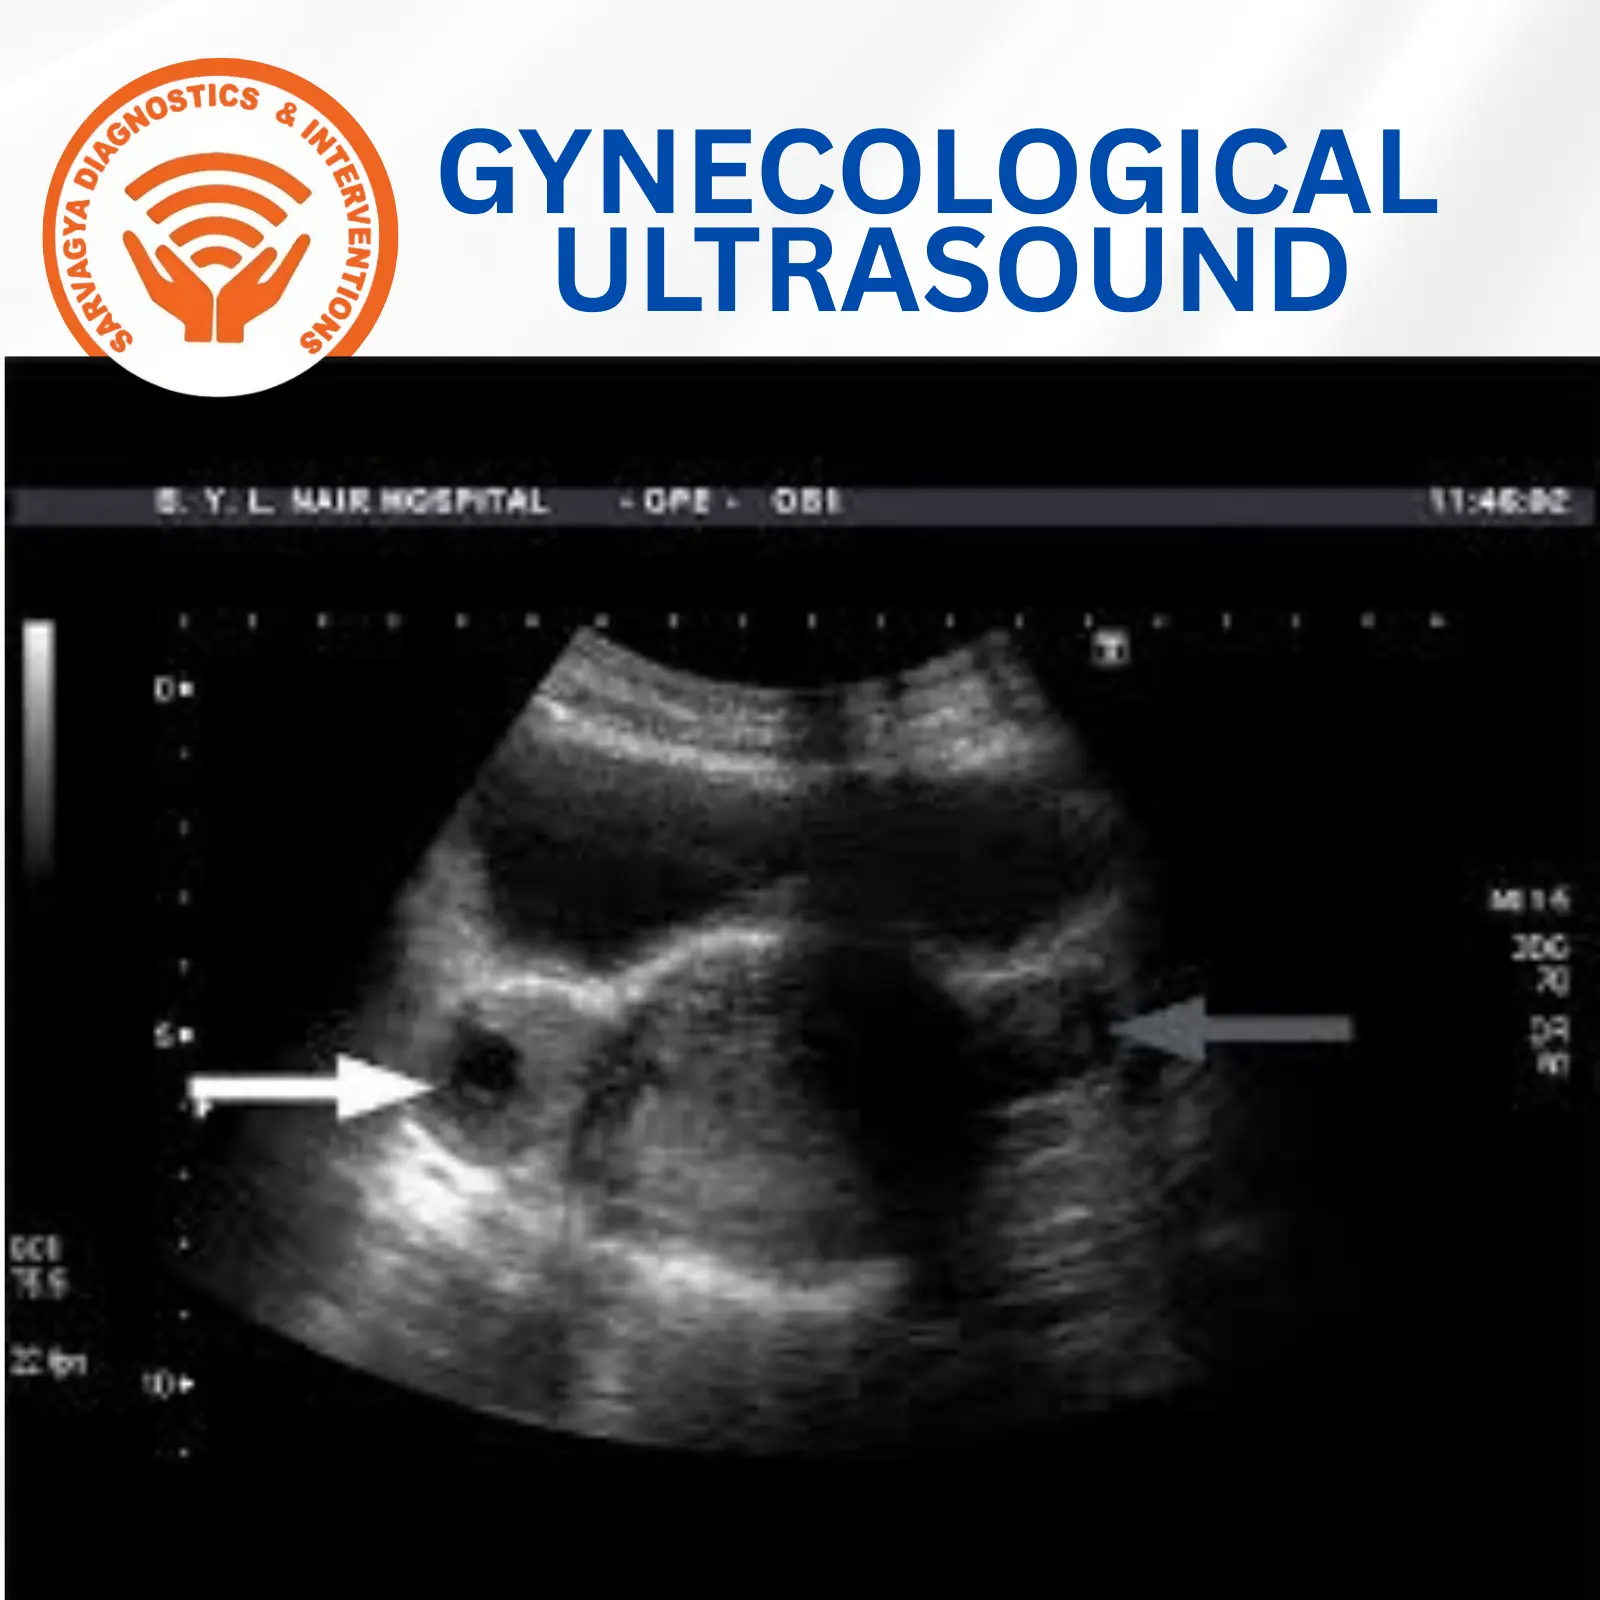

Special pelvic scans for all types of gynaecological problems are done here. We conduct TVS (transvaginal scans), high-end 3D scans. AFC (antral follicular count) and follicle monitoring studies at our clinic for problems such as menstrual disorders, infertility, pelvic pain, etc. At Sarvagya Diagnostic, we offer specialized Gynecological Ultrasound services designed to support women’s health at every stage of life. With advanced imaging technology and expert radiologists, we provide accurate and detailed assessments in a caring and comfortable environment.